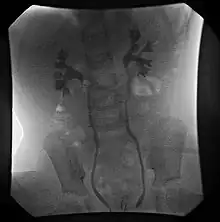

VCUG demonstrating bilateral Grade II (non-dilating) vesicoureteral reflux.

VCUG is the method of choice for grading and initial workup, while RNC is preferred for subsequent evaluations as there is less exposure to radiation. A high index of suspicion should be attached to any case where a child presents with a urinary tract infection, and anatomical causes should be excluded. A VCUG and abdominal ultrasound should be performed in these cases

Vesicoureteral reflux (VUR) is graded according to severity.[1]

• Grade I – reflux into non-dilated ureter

• Grade II – reflux into the renal pelvis and calyces without dilatation

• Grade III – mild/moderate dilatation of the ureter, renal pelvis and calyces with minimal blunting of the fornices

• Grade IV – dilation of the renal pelvis and calyces with moderate ureteral tortuosity

• Grade V – gross dilatation of the ureter, pelvis and calyces; ureteral tortuosity; loss of papillary impressions

The younger the patient and the lower the grade at presentation the higher the chance of spontaneous resolution. Approximately 85% of grade I & II VUR cases will resolve spontaneously. Approximately 50% of grade III cases and a lower percentage of higher grades will also resolve spontaneously.